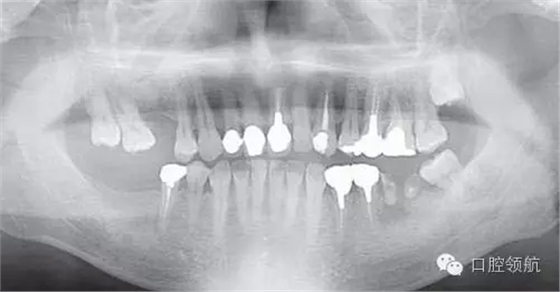

患者,38歲,男性,作為需要全面治療的患者來院?;局委熀?,右下頜磨牙區(qū)及右上頜磨牙區(qū),還有拔牙后的左下頜磨牙缺損區(qū),擬進行種植修復(fù)。圖1為初診時的曲面斷層影像,問診,模型診斷,曲面斷層檢查均未見異常,因此,最先在右下頜磨牙缺損區(qū),繼而在右上頜磨牙缺損區(qū)植入種植體,這些種植體愈合良好。

圖1 初診時的曲面斷層影像。